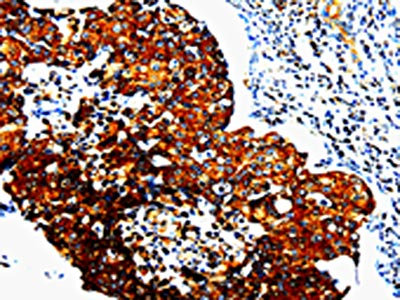

The image is immunohistochemistry of paraffin-embedded Human lymphoma tissue using CSB-PA699319(STAT5B Antibody) at dilution 1/10. (Original magnification: ×200)

The image is immunohistochemistry of paraffin-embedded Human breast cancer tissue using CSB-PA699319(STAT5B Antibody) at dilution 1/10. (Original magnification: ×200)